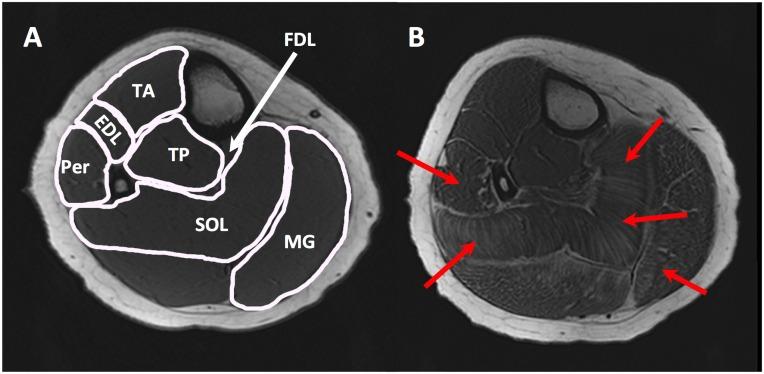

Lower leg muscles of thirty-two boys with DMD and sixteen age matched unaffected controls were imaged. Non-contractile content, contractile cross sectional area and non-contractile cross sectional area of lower leg muscles (tibialis anterior, extensor digitorum longus, peroneal, medial gastrocnemius and soleus) were assessed by magnetic resonance imaging (MRI). Muscle strength, timed functional tests and the Brooke lower extremity score were also assessed.

对32名患有DMD的男孩和16名年龄匹配的未受影响的对照者的小腿肌肉进行成像。通过磁共振成像(MRI)评估小腿肌肉(胫骨前肌、趾长伸肌、腓骨肌、腓肠肌内侧头和比目鱼肌)的非收缩成分、收缩横截面积和非收缩横截面积。还评估了肌肉力量、定时功能测试和布鲁克下肢评分。